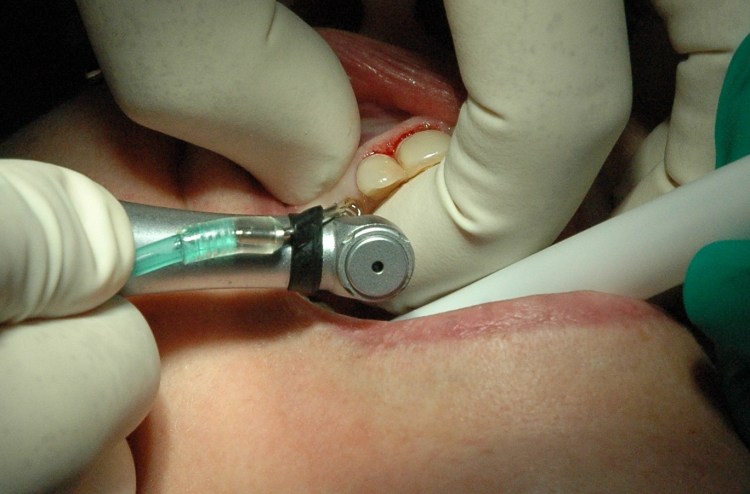

Note the surgical site was not immediately bleeding.

Implant site established … again with waterlase. Note the crown lengthened sites 12,11 are now bleeding. I also did some minor gingivoplasty on the the 22 which does not show up here.

Waterlase sites are good in that there are relatively blood free when you are working on them but do eventually bleed which I guess is good for the healing. The laser sites heal very well. In fact in this case the 11 site healed too well – (see photos later)